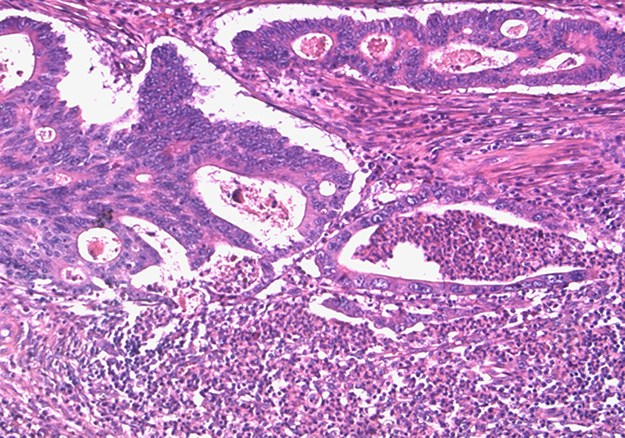

The same paraffin block on which molecular assays had been performed was chosen. Hematoxylin and eosin-stained sections of all formalin-fixed paraffin-embedded blocks were reviewed by a pathologist (MP) to confirm the presence of adequate tumor tissue and to evaluate tumor grade, pN status, pattern of advancing border, tumor budding, TANs, and IICs encompassing intra and peritumoral lymphocytes, macrophages, plasma cells. The IICs were evaluated as absent/mild when few cells were highlighted within the tumor and/or at the tumor-stroma interface, moderate/marked when the infiltrate was of greater density with the tendency to flow into plagues and infiltrate neoplastic epithelium. We evaluated TANs at the tumor-stroma interface and graduated as sporadic (Supplementary Figure 1) when only a few and spread granulocytes were present and massive when they were much more abundant and confluent into stromal or intraglandular abscesses (Figure 3). The study was approved by the institutional review board.

Figure 3: Massive TANs infiltration at tumoral edge with abscessual features.